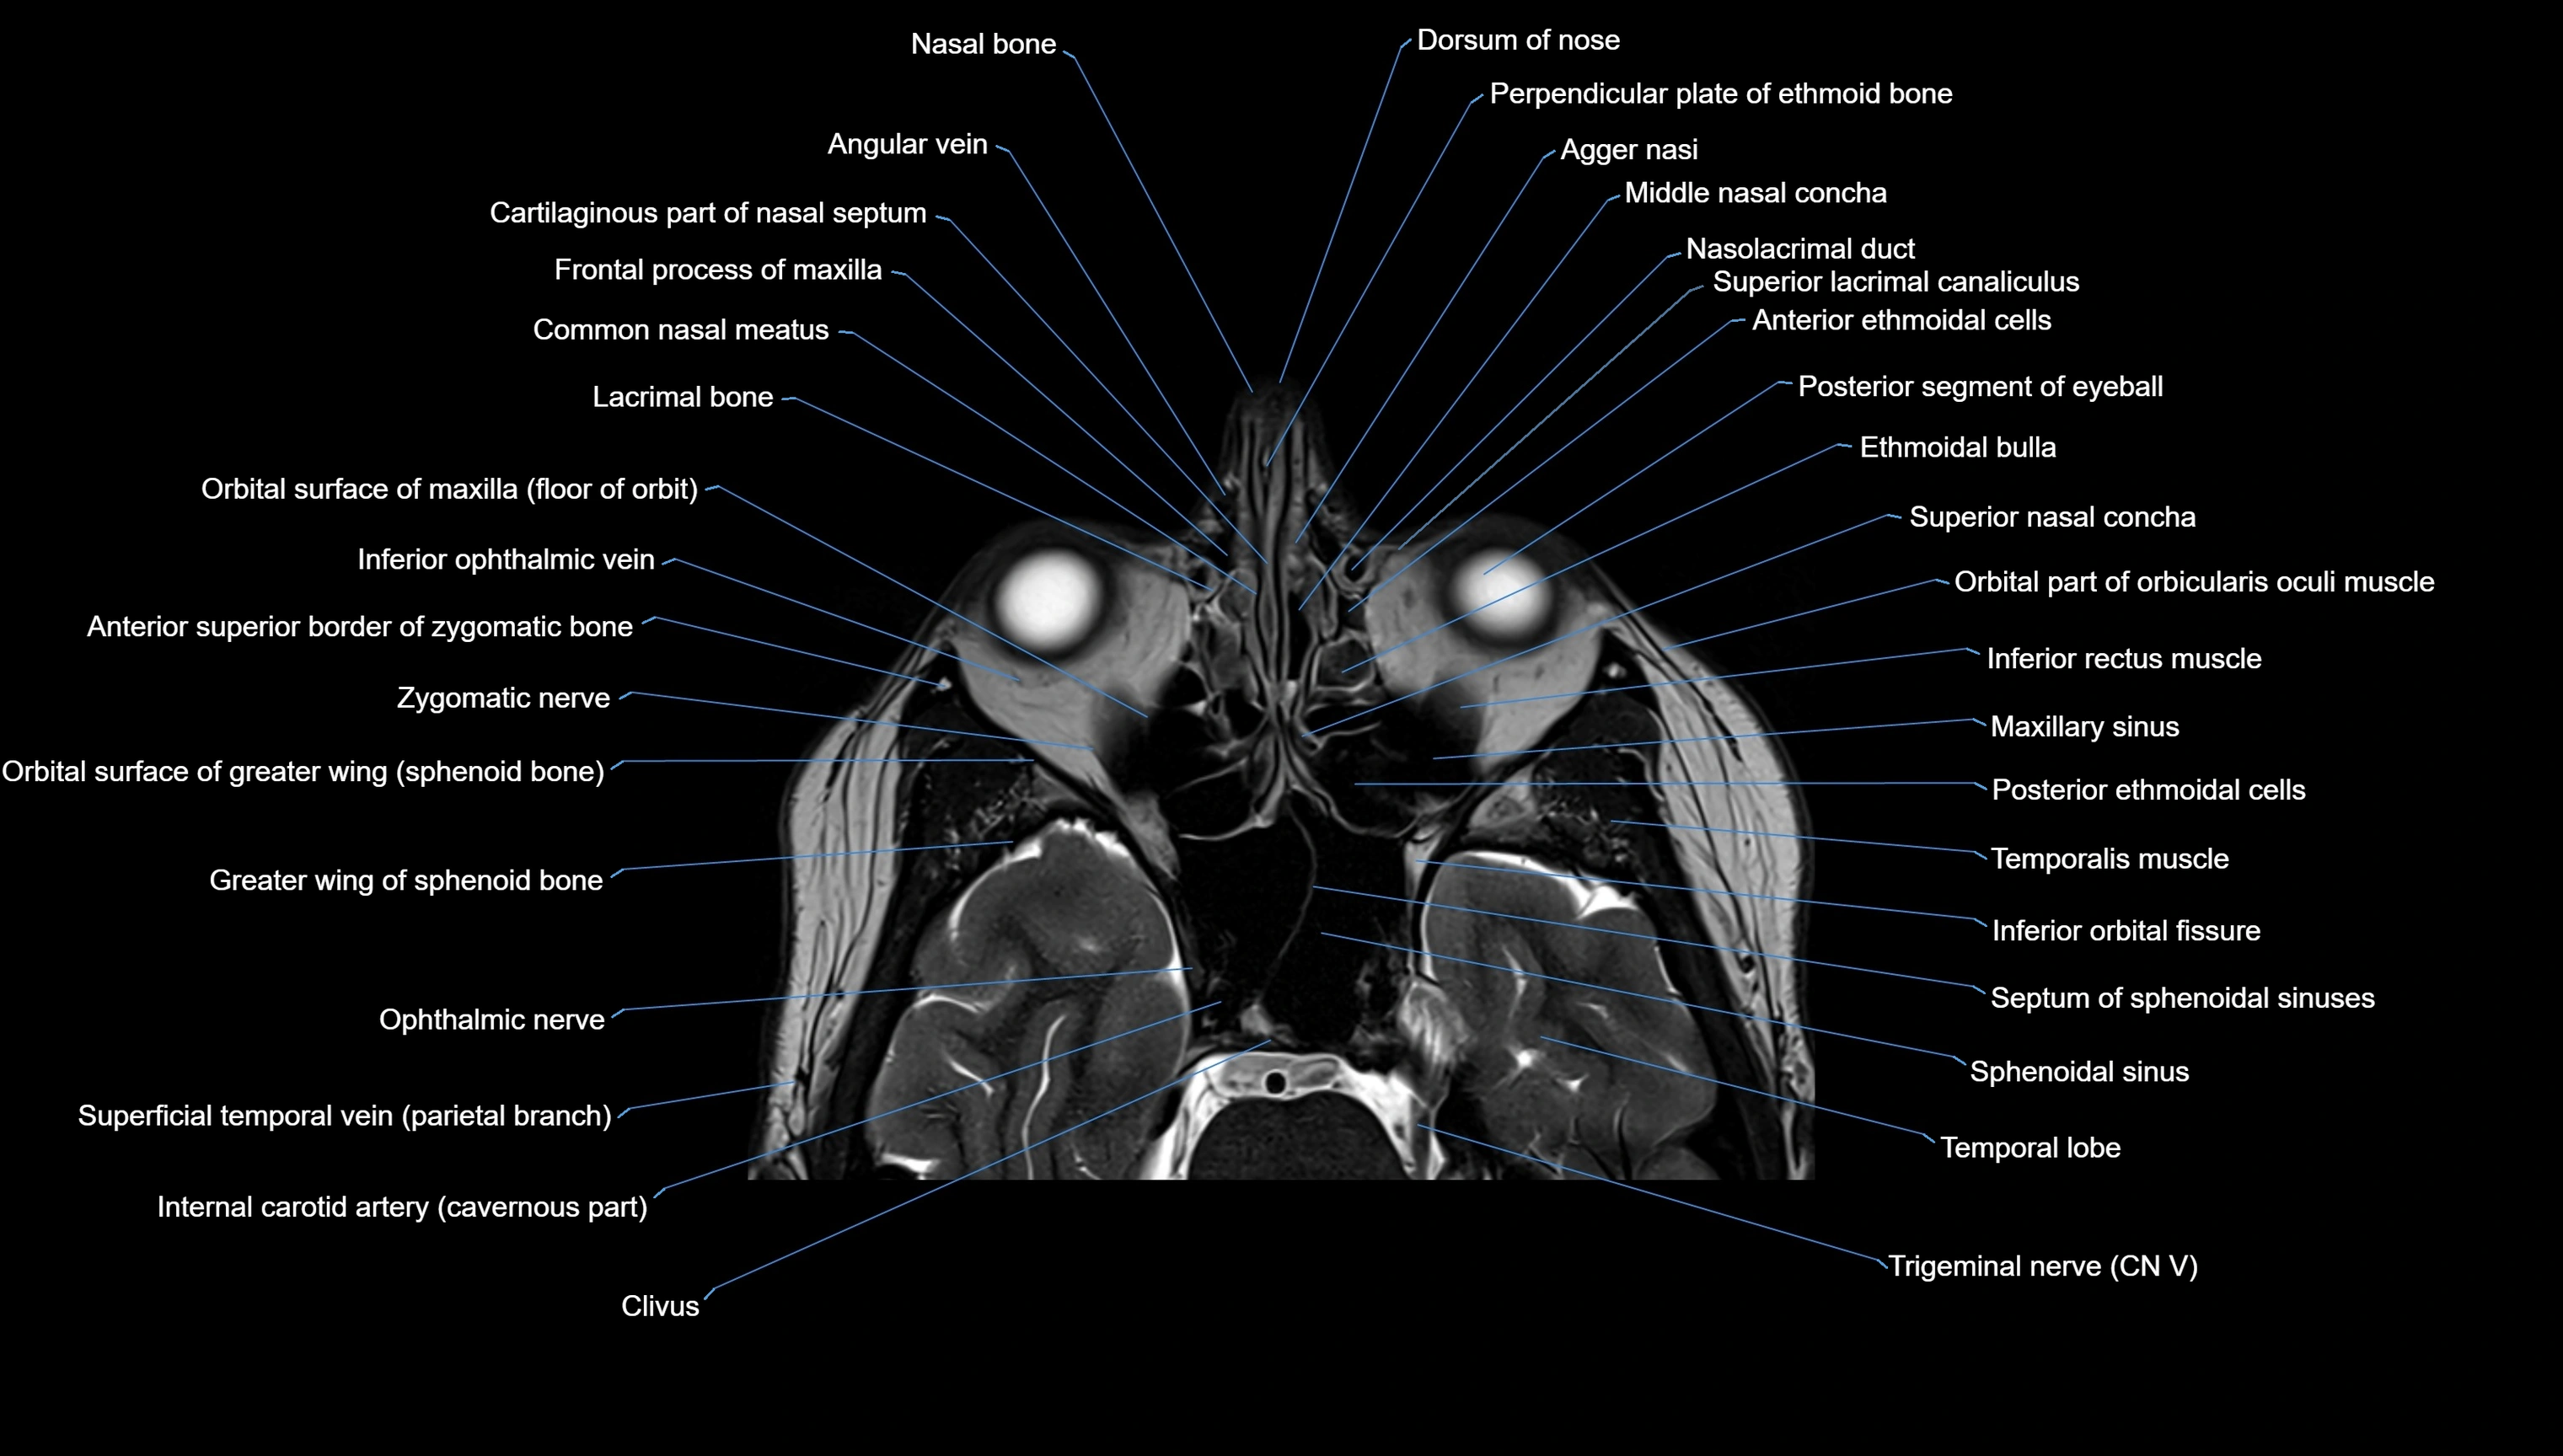

MRI images